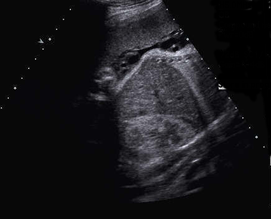

Above. Same tumor as above demonstrating a complex heterogeneous mass. Previous scans had demonstrated moderate vascularity. There was no evidence of fetal hydrops developed during the pregnancy.